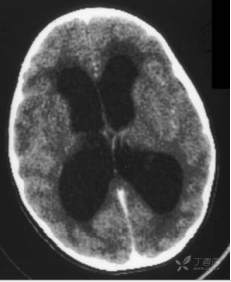

图9.13 头部非增强轴位CT显示梗阻性脑积水(脑室扩张)

图9.14 脑部轴位液体衰减反转恢复磁共振成像显示一个大的脑肿瘤,其占位效应导致颅内压升高。